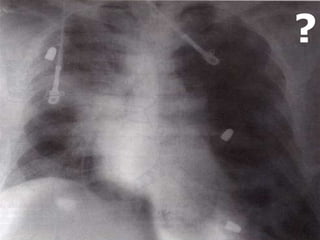

NEUMOTÓRAX TENSIÓN

Acumulación de aire en el espacio pleural, desde el

pulmón o por herida en la pared produciendo el

colapso del pulmón.

Dolor, falta de aire, dificultad respiratoria,

taquicardia, hipotensión, respiración paradójica

Desviación de la tráquea, ausencia de murmullo

vesicular, timpanismo, distensión de las

venas del cuello y cianosis.

¡¡¡PUNSION PLEURAL: 2o. EILMC Y SELLO DE AGUA!!!